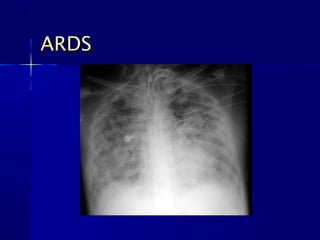

ARDS

   CXR CHARACTERISTICS

– Normal size heart

– No pleural effusion

– Ground Glass appearance

– Often normal early in the disease but may rapidly

progress to complete whiteout